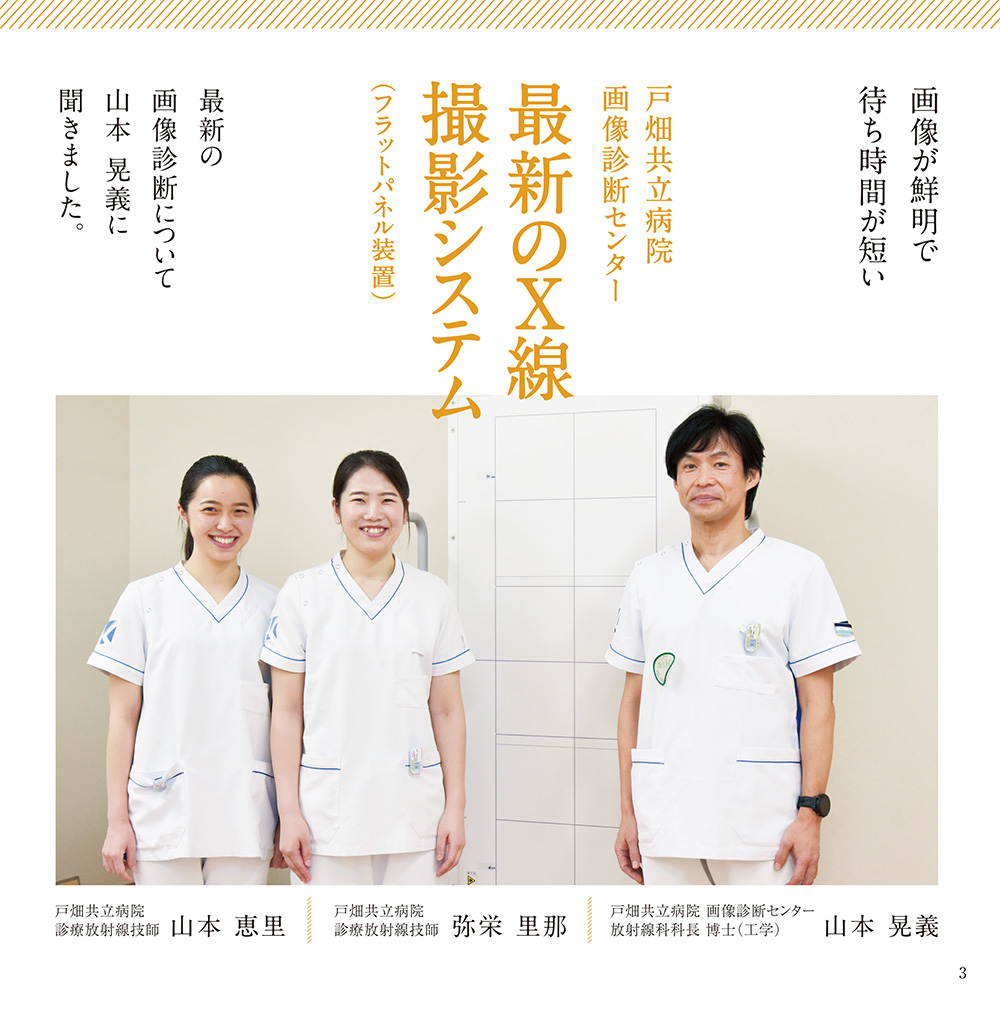

画像が鮮明で待ち時間が短い

戸畑共立病院画像診断センター

最新のX線撮影システム

(フラットパネル装置)

最新の画像診断について山本晃義に聞きました

レントゲン写真もデジタルカメラの時代!?

数十年前、私が小学生のころに親から古いカメラを譲り受け、それを持って外に出かけて様々な風景写真を撮影してました。写真屋さんへフィルムを持ち込み、数日後、きちんと写真が撮れているか、期待と不安でドキドキしながら引き取りに行ったものです。しかし、デジタルカメラの登場により、撮ったその場で写真を確認できるようになりました。今ではカメラ付きの携帯電話も出ており、誰でも簡単にキレイな写真が撮れるようにもなりました。

数十年前、私が小学生のころに親から古いカメラを譲り受け、それを持って外に出かけて様々な風景写真を撮影してました。写真屋さんへフィルムを持ち込み、数日後、きちんと写真が撮れているか、期待と不安でドキドキしながら引き取りに行ったものです。しかし、デジタルカメラの登場により、撮ったその場で写真を確認できるようになりました。今ではカメラ付きの携帯電話も出ており、誰でも簡単にキレイな写真が撮れるようにもなりました。

実は、このような技術がレントゲン写真にも利用されていることは、あまり知られていないと思います。レントゲン検査は体にX線を当て、体から出てきた様々な情報を持ったX線を特殊な装置で受けて写真にしますが、その際、撮った写真はその場でパソコンの画面上で確認できますので、まさにデジタルカメラのようなものですね。

実は、このような技術がレントゲン写真にも利用されていることは、あまり知られていないと思います。レントゲン検査は体にX線を当て、体から出てきた様々な情報を持ったX線を特殊な装置で受けて写真にしますが、その際、撮った写真はその場でパソコンの画面上で確認できますので、まさにデジタルカメラのようなものですね。

当院では昨年の7月、最新のX線検査の装置を導入しました。これまでの脊椎全体(首から腰の骨まで)や骨盤から足の先まで撮影する際、数回に分けて撮影する必要があり、検査時間も30分くらいかかっていました。この最新装置では、一回X線を当てるだけで脊椎全体や足全体を検査でき、しかも写真を瞬時にその場で確認できるので患者様の負担も随分少なくなりました。現在では検査時間が短くなり、患者様の待ち時間も大幅に短縮され、サービス改善に大きく貢献しております。検査を行うときに装置のことで気になることがありましたら最寄りのスタッフに遠慮なくお尋ねください。